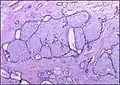

Histopathologic image of breast fibroadenoma. Core needle biopsy. H&E stain.

Fibroadenoma of the breast is a benign tumor composed of a biplastic proliferation of both stromal and epithelial components.[12][13] This biplasia can be arranged in two growth patterns: pericanalicular (stromal proliferation around epithelial structures) and intracanalicular (stromal proliferation compressing the epithelial structures into slit-like spaces).

These tumors characteristically display hypovascular stroma compared to malignant neoplasms.[2][14][9] Furthermore, the epithelial proliferation appears in a single terminal ductal unit and describes duct-like spaces surrounded by a fibroblastic stroma. The basement membrane is intact.[15]